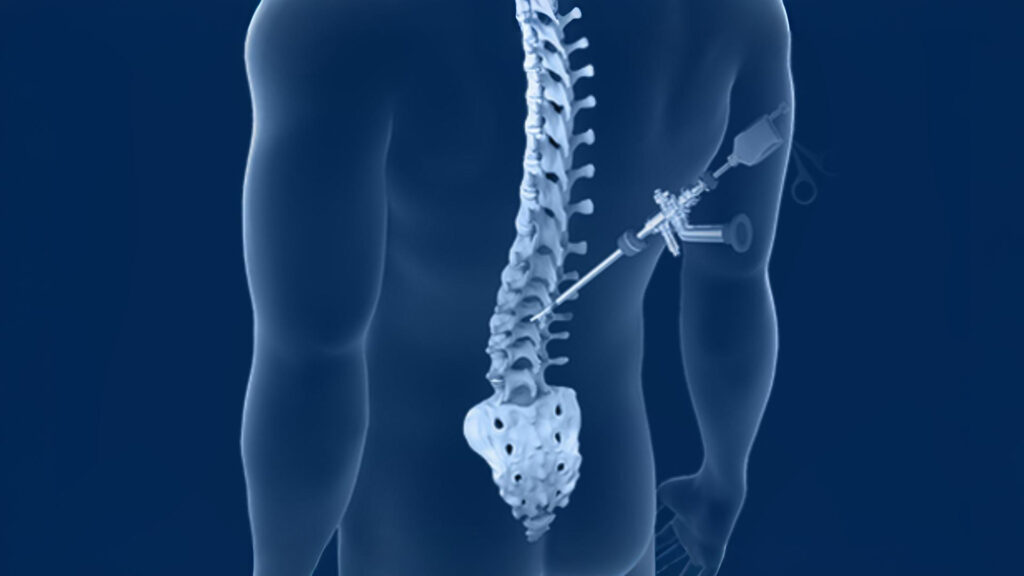

1. Minimally Invasive Spine Surgery (MISS)

Minimally Invasive Spine Surgery (MISS) by Dr. Rajesh Mishra is a modern technique to treat spinal problems with minimal damage to muscles and tissues. Unlike traditional open surgery, it uses small incisions, specialized instruments, and imaging technology for precise access. Dr. Rajesh Mishra’s expertise in MISS helps reduce blood loss, post-operative pain, infection risk, and shortens hospital stays. It is commonly used for herniated discs, spinal stenosis, degenerative disc disease, fractures, and some spinal deformities.

1. Endoscopic Spine Surgery

Endoscopic Spine Surgery by Dr. Rajesh Mishra is a minimally invasive procedure that uses a small camera (endoscope) and specialized instruments to treat spinal conditions. Unlike traditional open surgery with large incisions, it requires only tiny cuts, minimizing damage to muscles and tissues. Dr. Rajesh Mishra’s expertise ensures a clear, magnified view of the spine, enabling precise treatment of herniated discs, spinal stenosis, nerve compression, and degenerative spine problems. Benefits include less blood loss, reduced pain, minimal scarring, and shorter hospital stay.